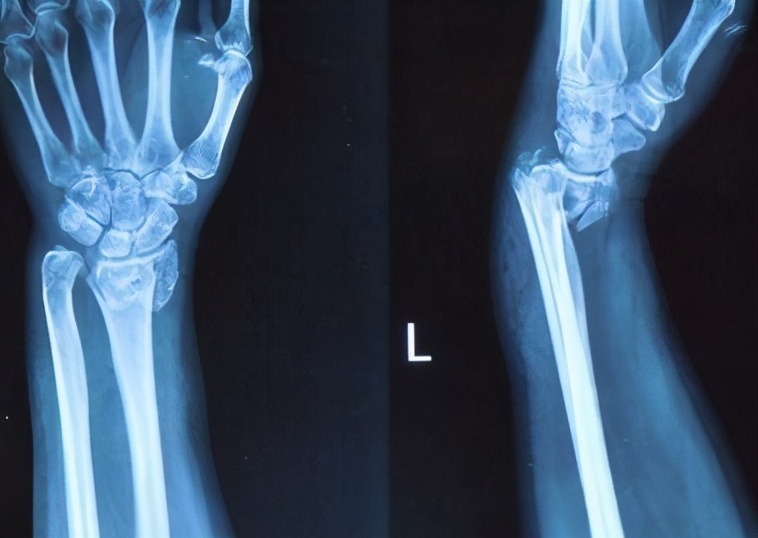

- 骨折

日常生活中,受到轻微外伤直接导致骨折,常见骨折发生部位:腰胸椎、股骨颈、桡骨、肱骨,如不及时进行有效干预,一年内极可能再次发生骨折,髋部骨折是较严重的骨质疏松性骨折。